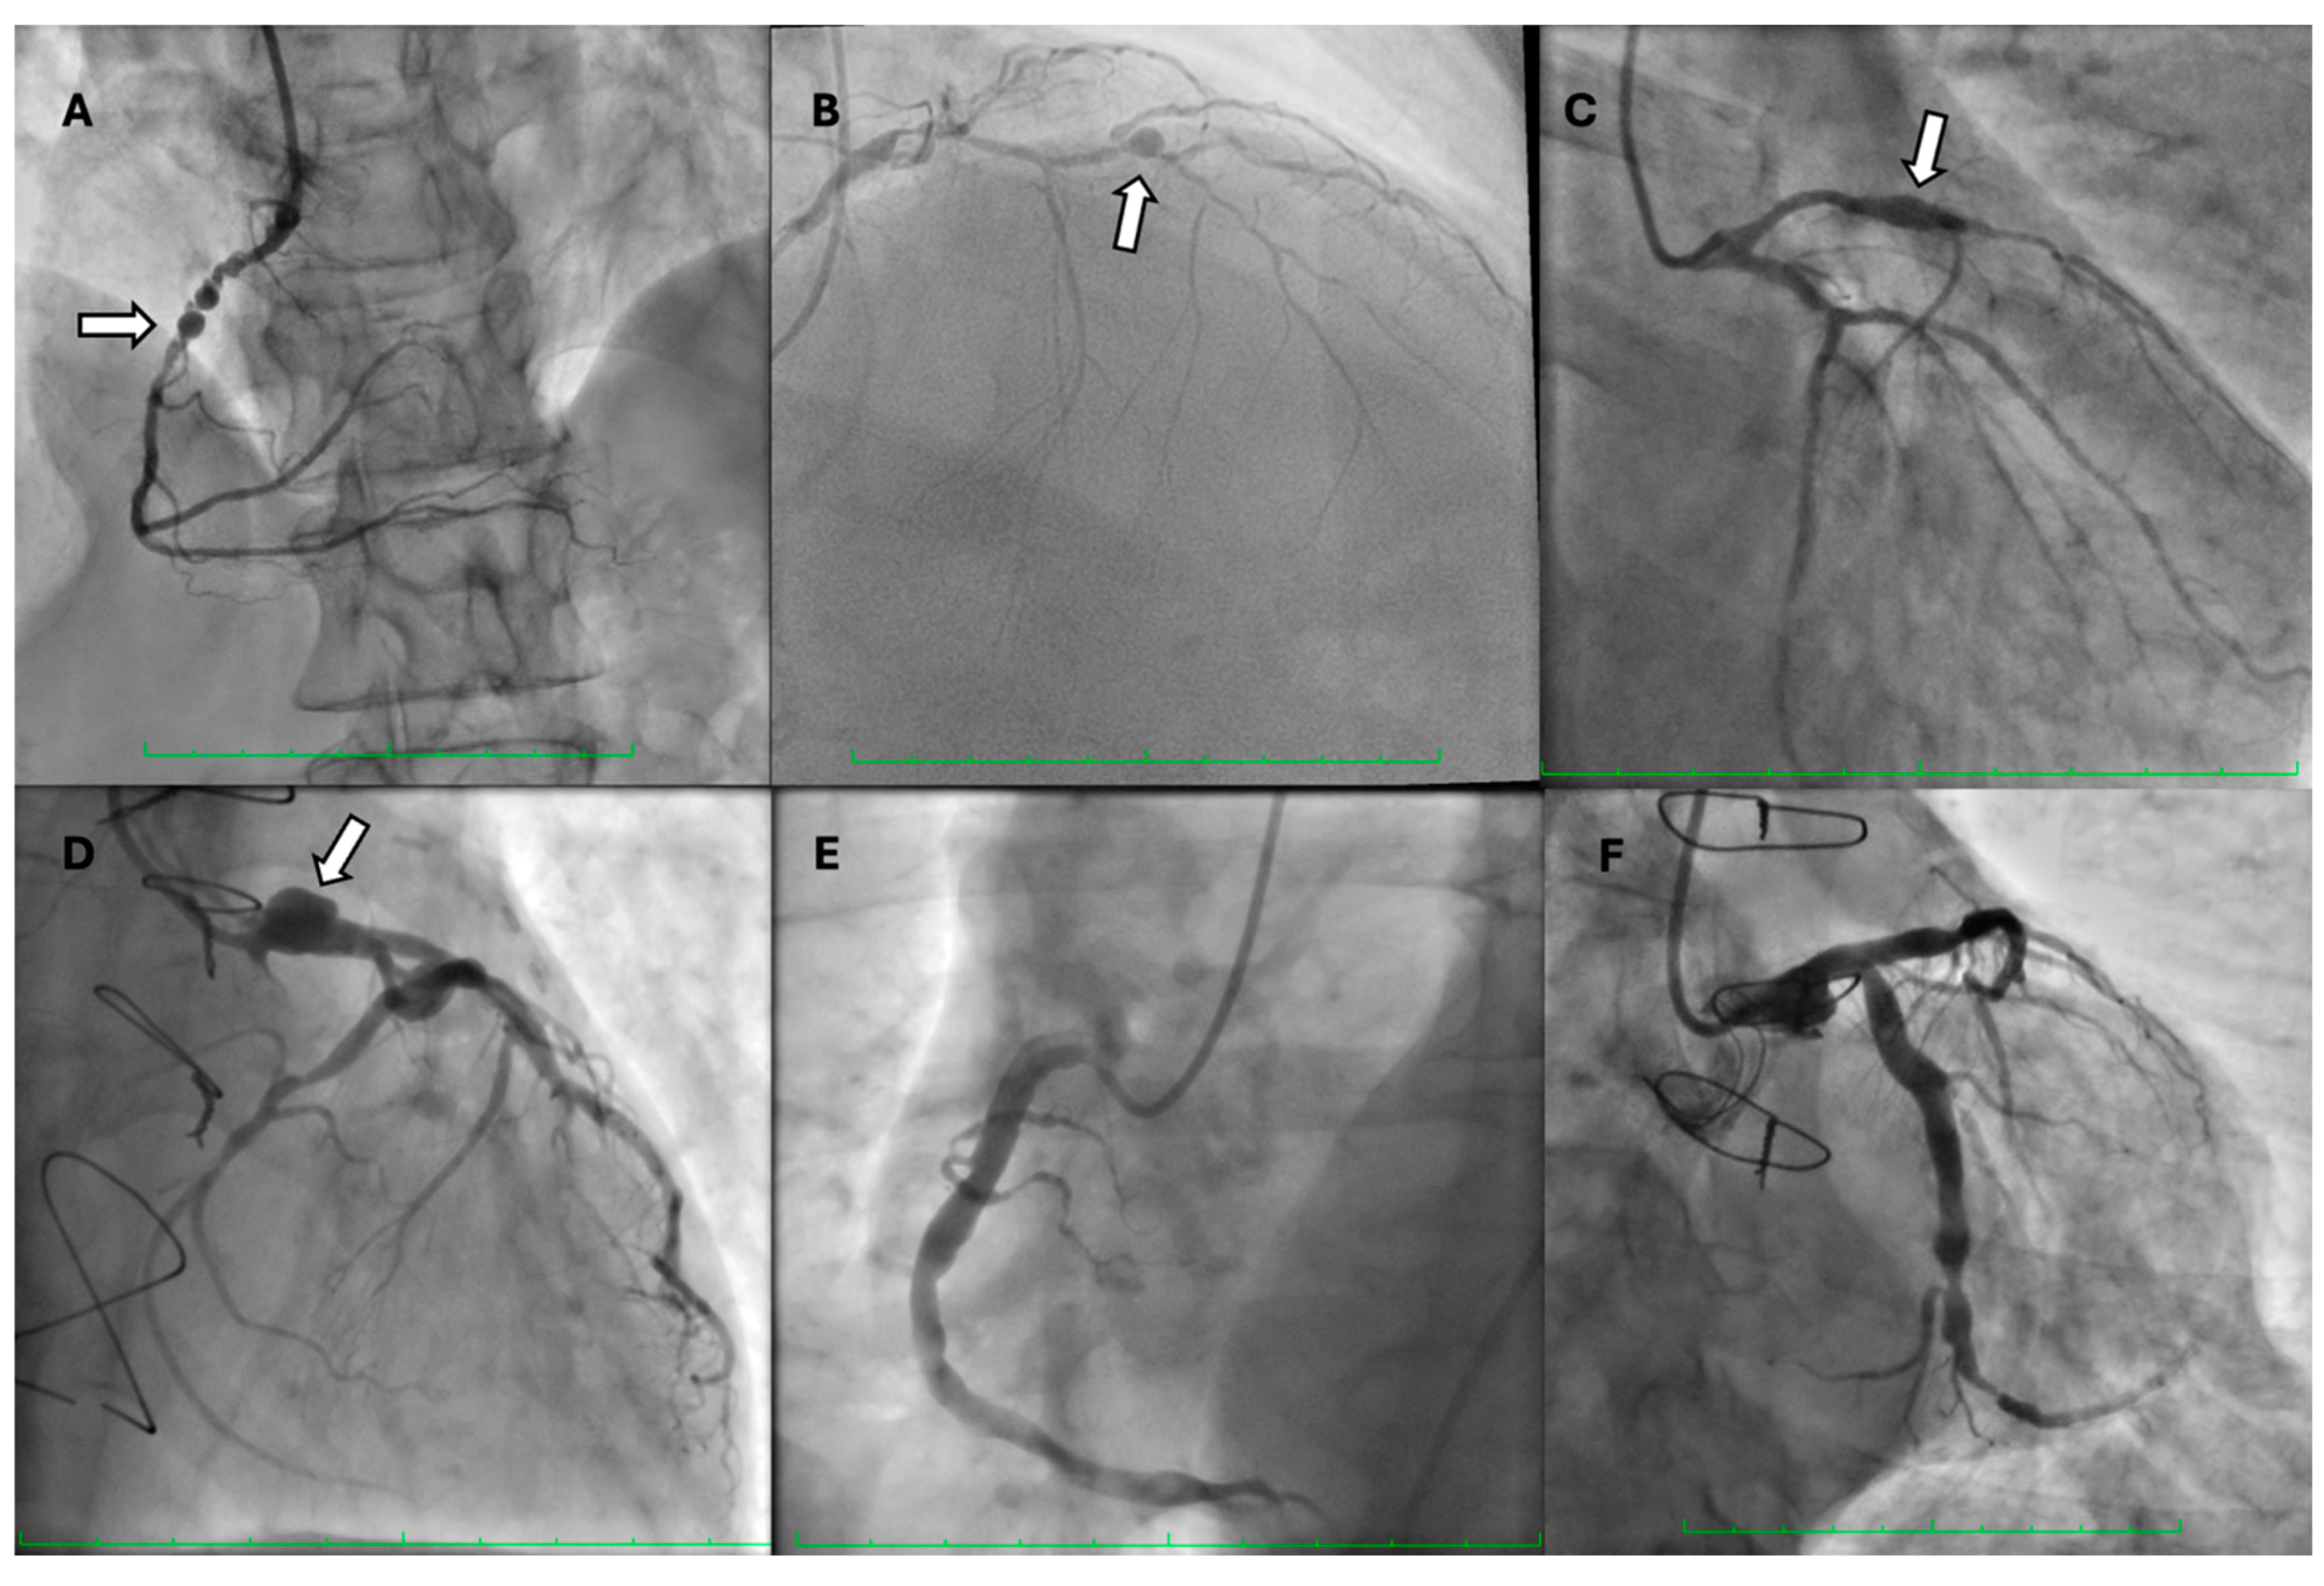

- Win, H.K.; Polsani, V.; Chang, S.M.; Kleiman, N.S. Stent-assisted coil embolization of a large fusiform aneurysm of proximal anterior descending artery: Novel treatment for coronary aneurysms. Circ. Cardiovasc. Interv. 2012, 5, e3–e5. [Google Scholar] [CrossRef] [PubMed][Green Version]

- Spiotta, A.M.; Wheeler, A.M.; Smithason, S.; Hui, F.; Moskowitz, S. Comparison of techniques for stent assisted coil embolization of aneurysms. J. Neurointerv. Surg. 2011, 4, 339–344. [Google Scholar] [CrossRef] [PubMed]